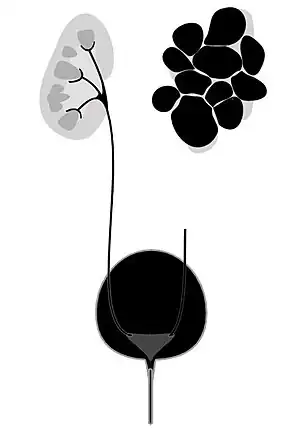

| Diagram of multicystic dysplastic kidney | |

Kidney dysplasia, also known as multicystic dysplastic kidney (MCDK), is when the internal structures of one or both kidneys do not form properly during early development.[1] If one kidney is affected, often there are no symptoms, though in some cases the kidney enlarges and causes pain.[1] Complications can include hydronephrosis, high blood pressure, urinary tract infections (UTI), or kidney failure.[1] If both kidneys are severely affected the child may die around the time of birth.[1]

Right dysplastic kidney with the largest cyst size measuring 33.16mm

Right dysplastic kidney with the largest cyst size measuring 33.16mm -